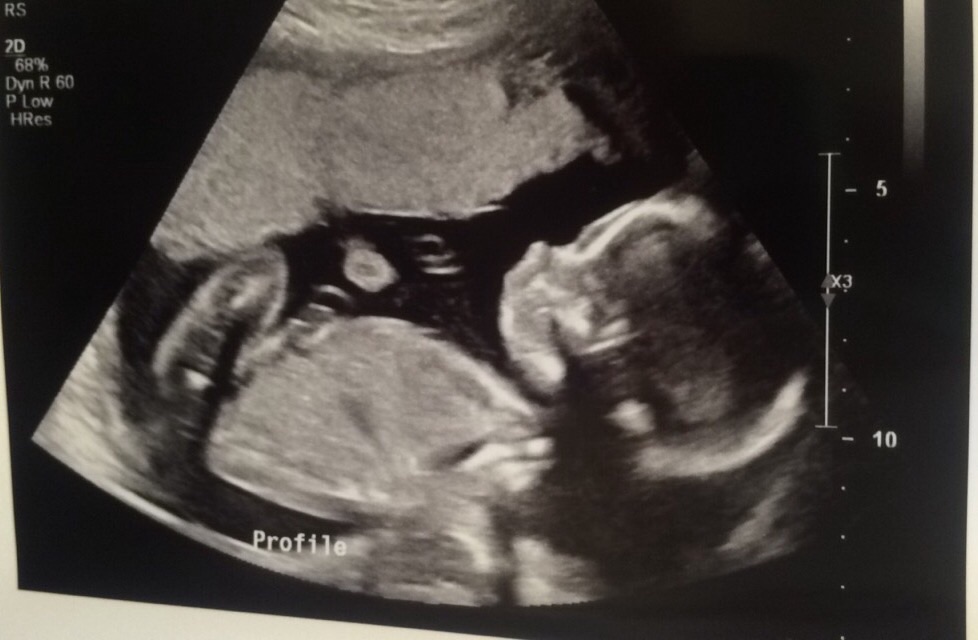

I just thought I'd pop in & post that I'm Team Pink, even though my new due date is technically Nov 5th now. My original EDD was Oct 16th based on my LMP, hence my screen name. Hope you ladies are doing well!